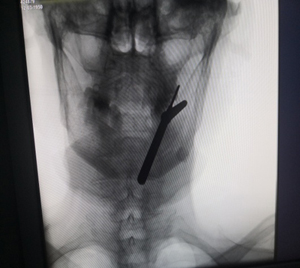

手术充分减压

3.安全性高:全程X线辅助定位+可视化屏幕,手术采用局部麻醉,可及时与患者沟通,降低高龄患者麻醉风险及神经损伤几率。